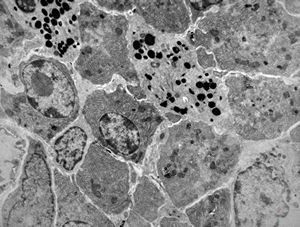

F,68y. | caecum - carcinoid